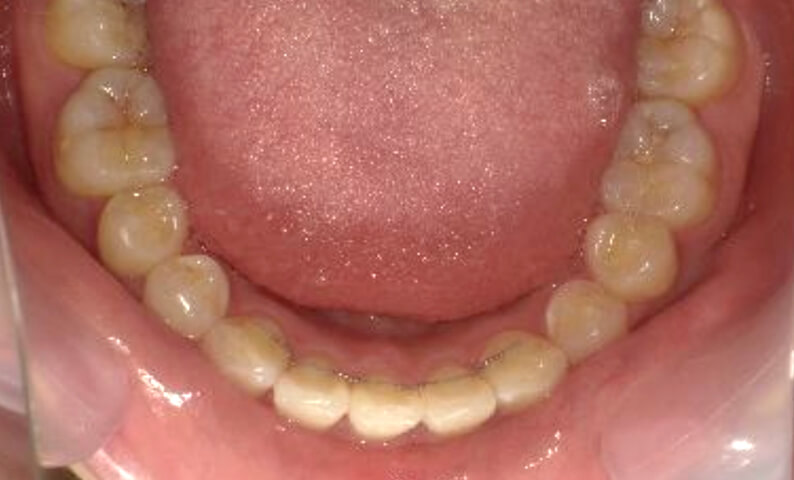

症例_025 上下顎の部分矯正

治療期間:13ヶ月金額:51万円+税女性前歯のガタガタ出っ歯